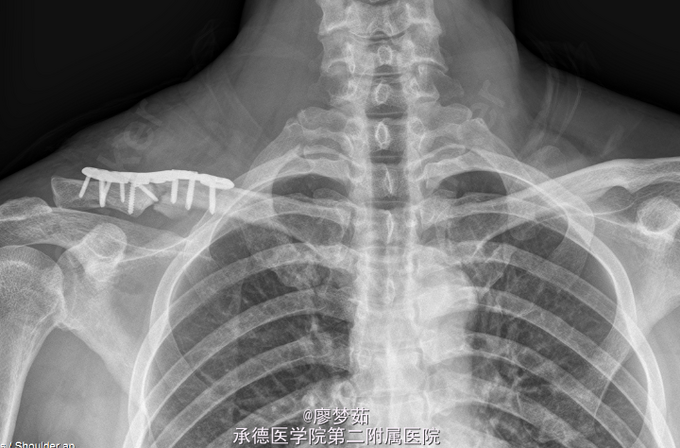

初步诊断: 右侧锁骨粉碎性骨折.全麻下行行“右锁骨骨折切复内固定术”。取右肩部锁骨前外侧切口长约12cm,逐层暴露至骨折端,见锁骨中远段粉碎性骨折,骨折端移位,有一较大碟形骨块,冲洗创面,清除血肿,予复位,予一枚螺钉固定碟形骨块,恢复锁骨长度,放置锁骨远端解剖锁定钢板一块,远近端分别予锁钉螺钉内固定。

切口敷料干燥无渗出,末梢感觉血运可,术后复查平片示,内植物位置佳。若有局部红肿,疼痛,畸形等异常情况及时就诊。